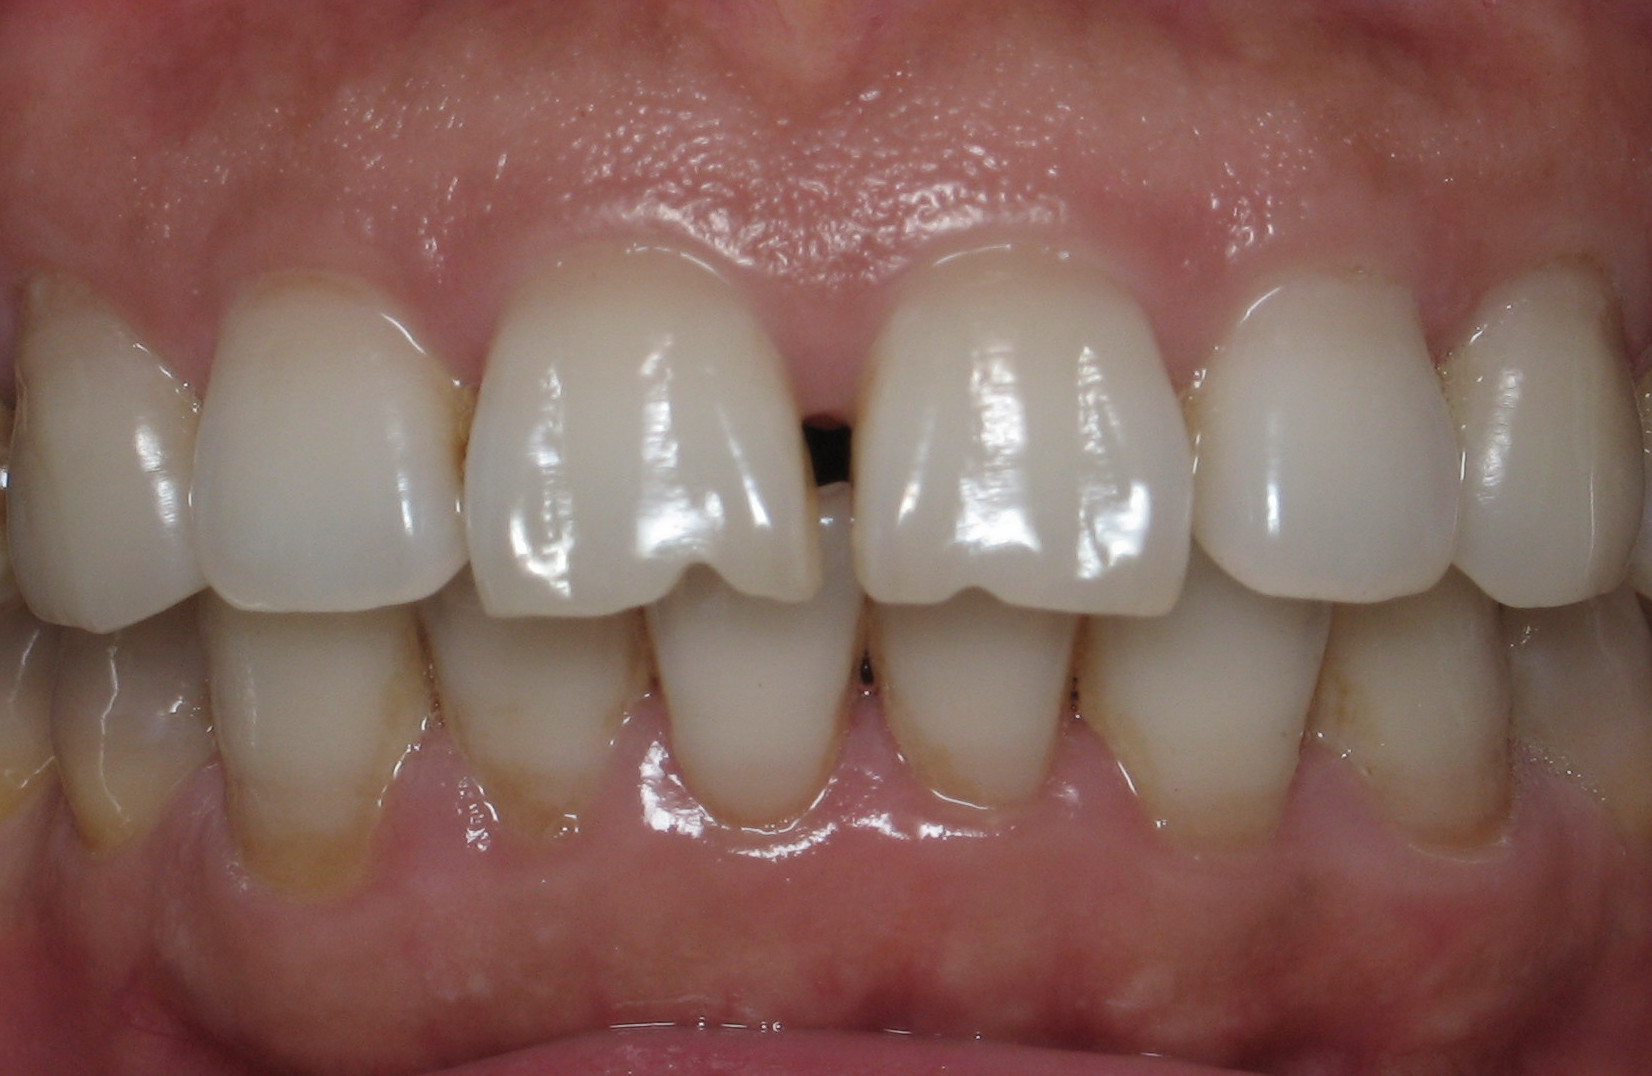

Orthodontic Treatment X-ray - Before

After Series of Teeth Extractions, Upper Left Canine Unerupted.

Ready to Start Ortho Treatment